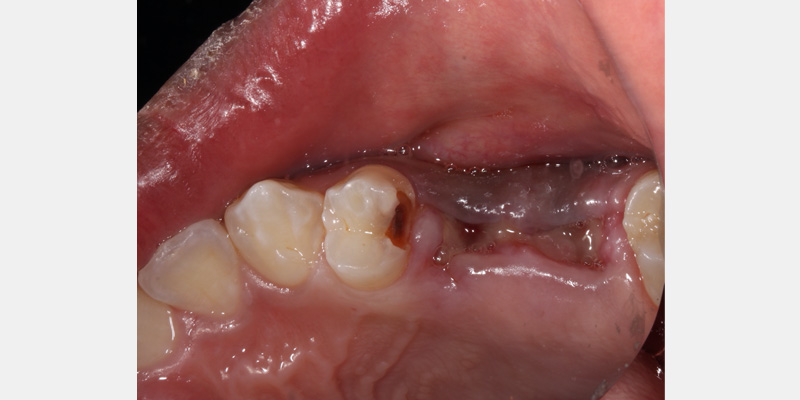

Rubber dams can be very useful for everyday restorative dentistry procedures, such as cases where deep carious lesions present a risk of pupal exposure, restorative procedures next to recent extraction sites, and anterior cases where tissue retraction is necessary.